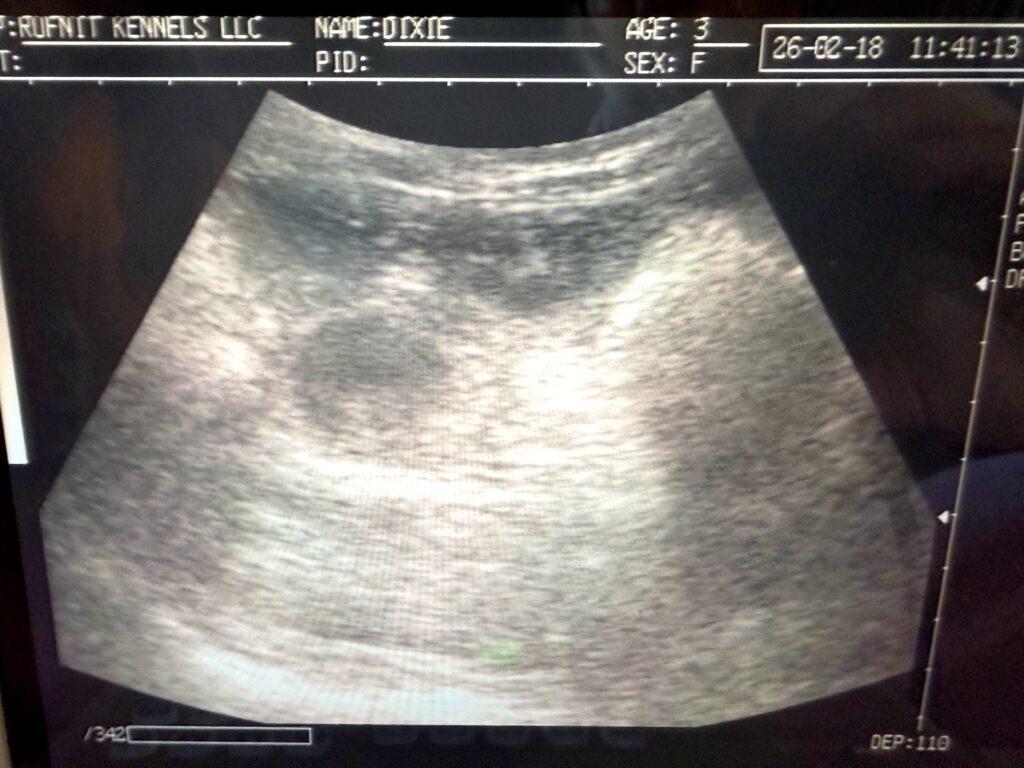

Click here: Rufnit “I” Litter Pre-whelp ultrasound! 03-07-26